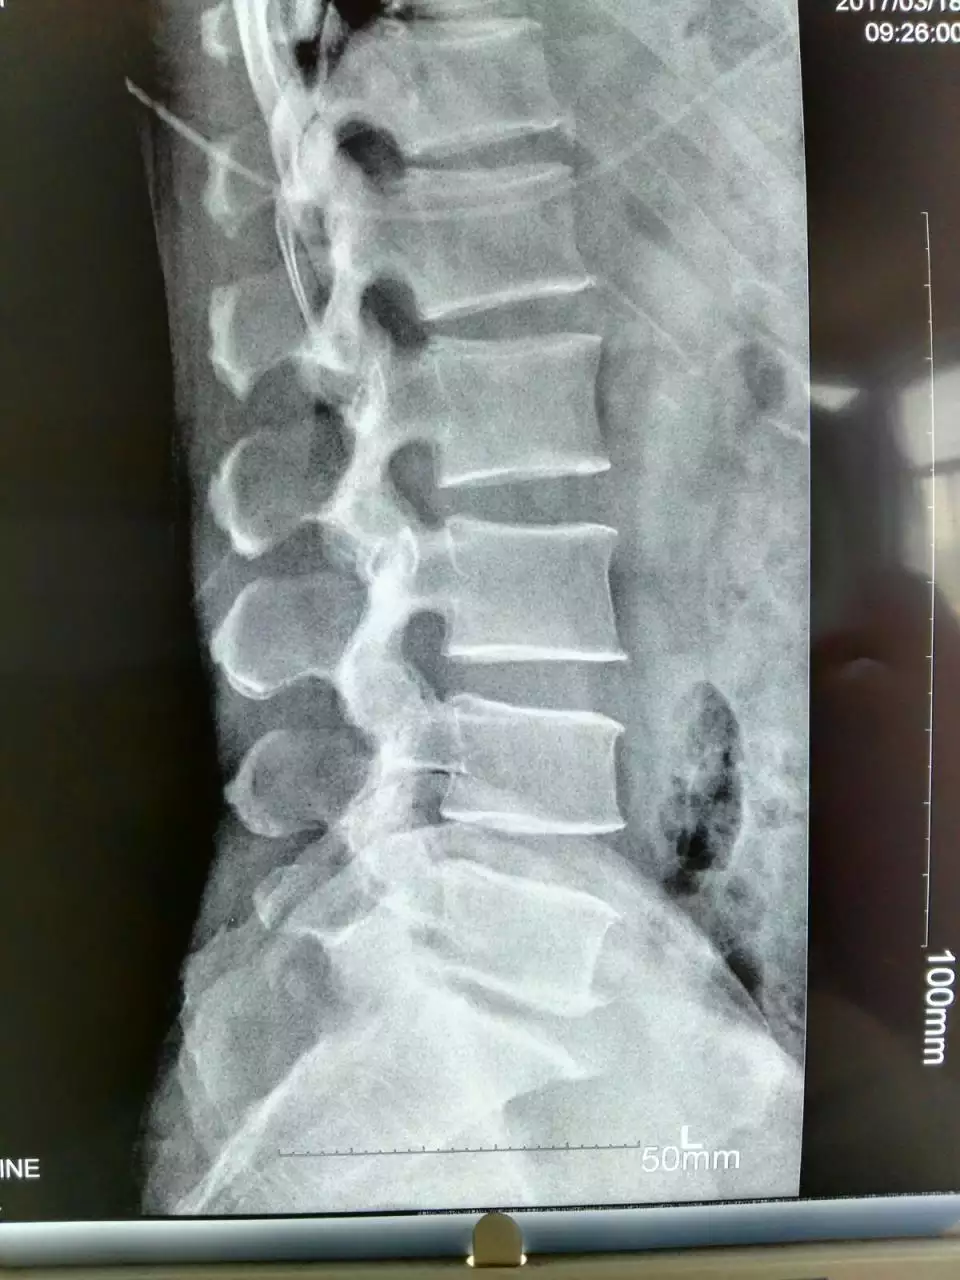

腰5骶1突出正確睡姿圖片

1、腰5骶1突出正確睡姿圖片:,正確的睡覺姿勢是怎麼樣的呢?

腰間盤突出的正確睡姿圖是什麼樣子的?怎麼緩解?